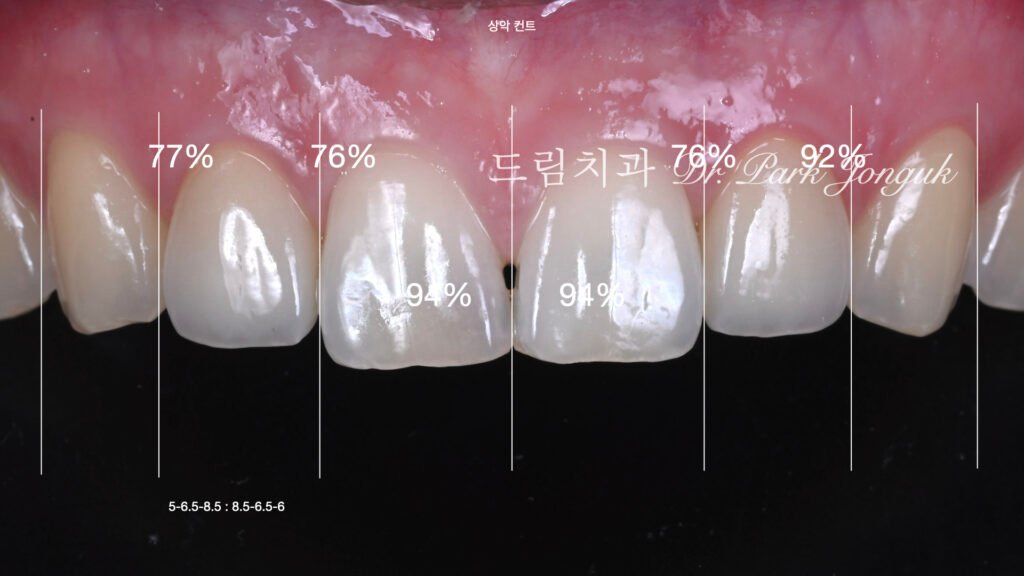

2.1 초진 상태 및 기존 보철물 진단 (사진 1, 2)

[사진 1, 2 참조] 환자분은 말할 때 치아가 거의 노출되지 않는 전형적인 옥니 상태였습니다. 양측 측절치(Lateral Incisor)는 이미 크라운 치료가 되어 있었으나, 주변 자연치와 색상이 어우러지지 않았고 형태적으로도 미흡했습니다.

4. 핵심 기술: 보철물 간의 색상 매칭 (Shade Matching)

가장 큰 기술적 도전은 **’크라운과 라미네이트의 색을 똑같이 맞추는 것’**이었습니다.

- 재질의 차이: 크라운은 지대치를 완전히 덮는 두께를 가지며, 라미네이트는 치아 앞면에 붙는 0.1~0.3mm의 얇은 막입니다.

- Handmade Build-up: 기계 절삭 방식으로는 이 차이를 극복하기 어렵습니다. 숙련된 기공사와 전문의가 협업하여 세라믹 파우더를 층층이 쌓아 올리는 핸드메이드 빌드업 방식을 통해, 서로 다른 두께에서도 빛이 동일하게 반사되도록 광학적 성질을 맞추었습니다.